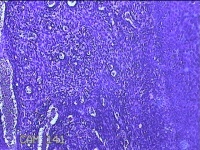

宫颈赘生物

性别

女

年龄

49岁

临床诊断

人乳头瘤病毒感染

一般病史

宫颈HPV阳性TCTLSLL

标本名称

大体所见

灰白粉红色肿物1.2x0.8x0.2cm两个,表面光滑。

图4